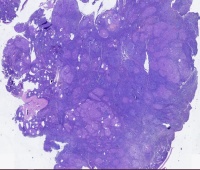

淋巴结转移癌,是非角化未分化癌吗

性别

男

年龄

59岁

临床诊断

淋巴结增大

一般病史

淋巴结增大2年,逐渐增大

标本名称

右颈部淋巴结

大体所见

1.5*1.0cm,灰白色

考虑前者

淋巴结转移性癌,高度怀疑鼻咽部来源